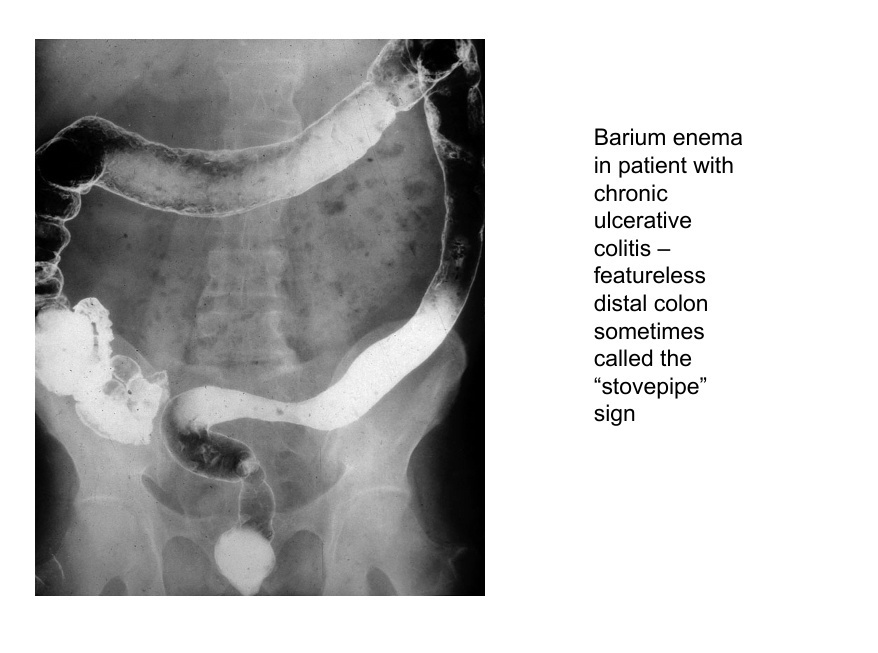

UC scan

A

stovepipe sign